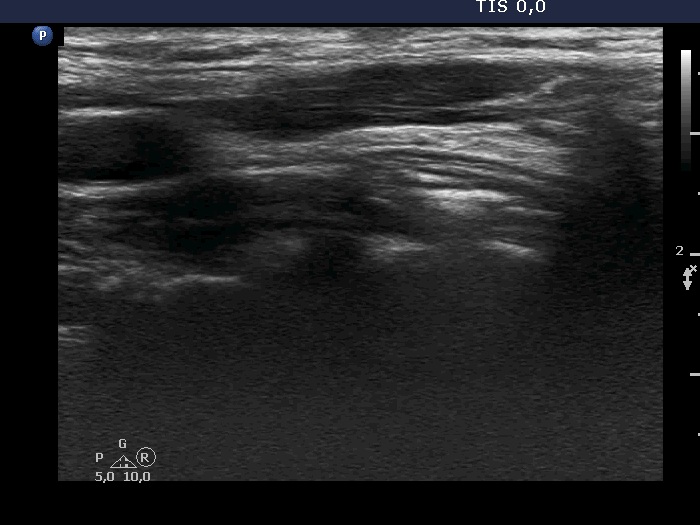

Case 1738 (ultrasonographic picture 9)

Left lobe, longitudinal scan.